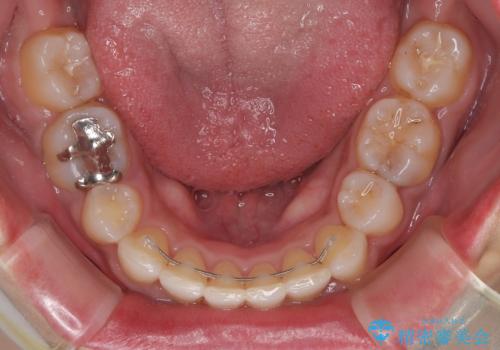

抜歯矯正で口が閉じやすく|ディープバイトと叢生を改善した症例

- 下顎前歯部には叢生が認められ、口を自然に閉じにくい状態でした。また、噛み合わせが深い「ディープバイト」の状態で、見た目だけでなく将来的な奥歯への負担も懸念されました。

口元の突出感を改善するため、上下左右の小臼歯4本を抜歯する矯正治療を計画しました。

「矯正装置が目立つのは避けたい」というご希望があったため、プラスチックブラケット+コーティングワイヤーを使用した審美装置を選択しました。